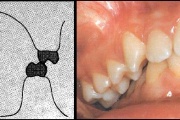

Vali sind huvitav pilt ja me näitame sellega seotud haigust ja sümptomeid